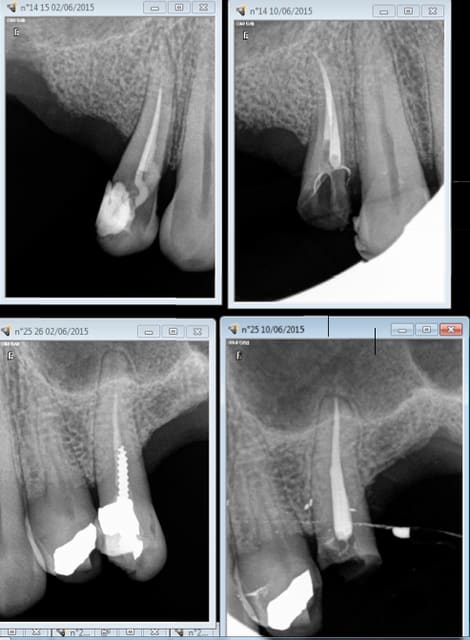

Mon exemple, patiente qui a une CIV depuis trente ans et dont la céramique a sauté. Le traitement ne va pas au bout et n'est pas très dense mais pas de symptomatologie ni d'image apicale. Alors, RTE ou pas?

14 était fracturée initialement,, motif de la consult.

Alors RTE ou pas RTE ( meme patient) ? Pas trop mal cette endo, on est jamais à l'abri d'un coup de bol ! -))))